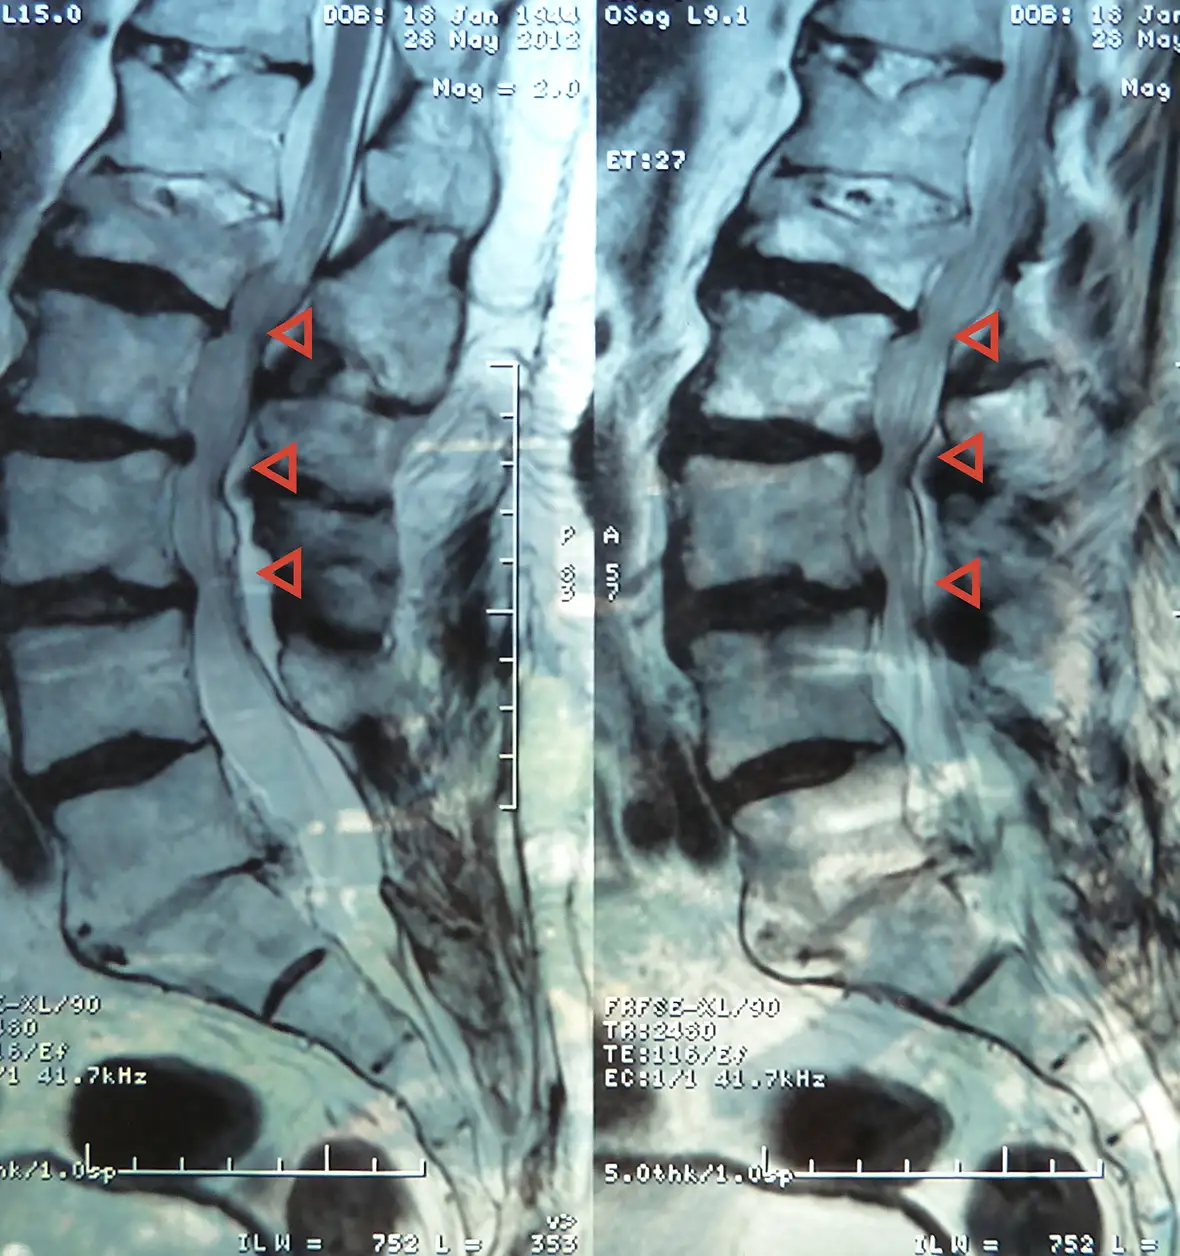

Public domain lumbar X-ray showing spinal stenosis at the lower vertebrae—highlighting the narrowing of the spinal canal and compression of nerve roots. Restoring balanced soft-tissue function around these structures can reduce pressure and improve mobility.